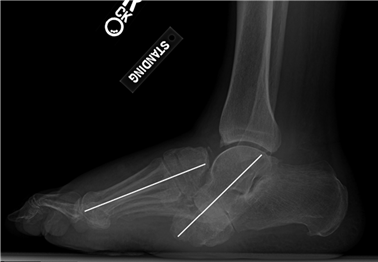

Weight-bearing anteroposterior (AP), lateral, and sesamoid axial radiographs are mandatory. On the AP view, the surgeon measures the Hallux Valgus Angle (HVA, normal < 15°), the Intermetatarsal Angle (IMA, normal < 9°), and the Distal Metatarsal Articular Angle (DMAA). The lateral view is scrutinized for Meary's angle (talo-first metatarsal angle) to identify midfoot collapse, as well as the presence of dorsal osteophytes indicative of hallux rigidus. The sesamoid axial view is critical for assessing the degree of sesamoid subluxation and the integrity of the crista.

Image